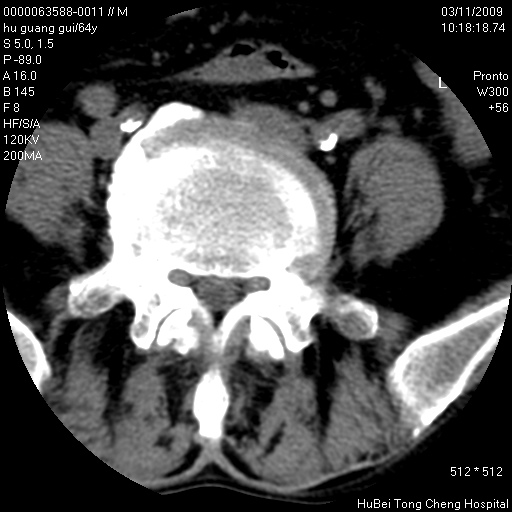

患者 男,64岁。腰痛十余天。(临床未提供其他病史)

临床诊断:腰痛原因待查(腰椎间盘突出症?)。

腰椎间盘ct轴位平扫(层厚5mm,层距4mm),图像如下:

腰椎退行性变,腰4—5椎间盘膨出。

右侧骶骨侧块骨侵蚀,骶髂关节骨性关节面破坏,并见软组织肿块,考虑骨转移瘤可能,进一步检查。

1.腰椎退行性变,腰4—5椎间盘膨出。

2.右侧骶骨侧块骨侵蚀,骶髂关节骨性关节面破坏,并见软组织肿块,考虑:脊索瘤,骨转移瘤可能,进一步检查。